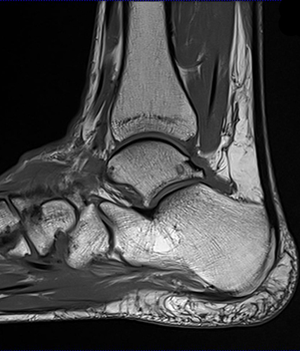

<¼Õ, ¹ß¸ñ MRI>

¼Õ, ¹ß¸ñ ÁúȯÀ̶õ?

¼Õ, ¹ß¸ñÀ» ÁöÅÊÇÏ´Â ÀÎ´ë ¹× ±ÙÀ°µéÀÌ ¿ÜºÎÀÇ Èû ¶Ç´Â Æò¼Ò »ýȰ½À°üÀ¸·Î ÀÎÇÏ¿© ¼Õ»óµÈ °æ¿ì¸¦ À̾߱â ÇÕ´Ï´Ù.